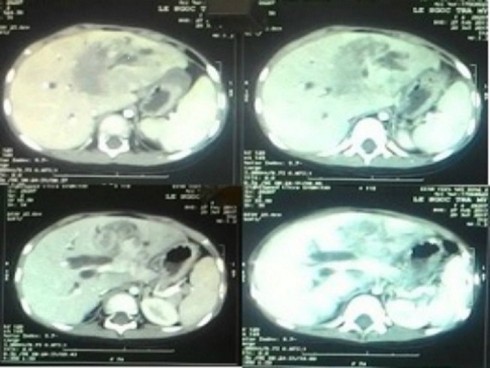

Bệnh nhi được đưa đến BV Nhi Đồng 2 trong tình trạng vàng da kéo dài tăng dần khoảng 2 tháng và đi cầu phân trắng. Sau khi chụp CT scan vùng bụng, các BS đã phát hiện một khối u gan rất lớn, chiếm hết toàn bộ gan trái, gây ra tình trạng vàng da tắc mật bất thường của bé.